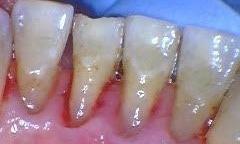

Before picture shows heavy build up of calculus and stains around the lower front teeth. After deep cleaning, the picture shows the calculus are removed and the gum can heal and recover from chronic inflammation.